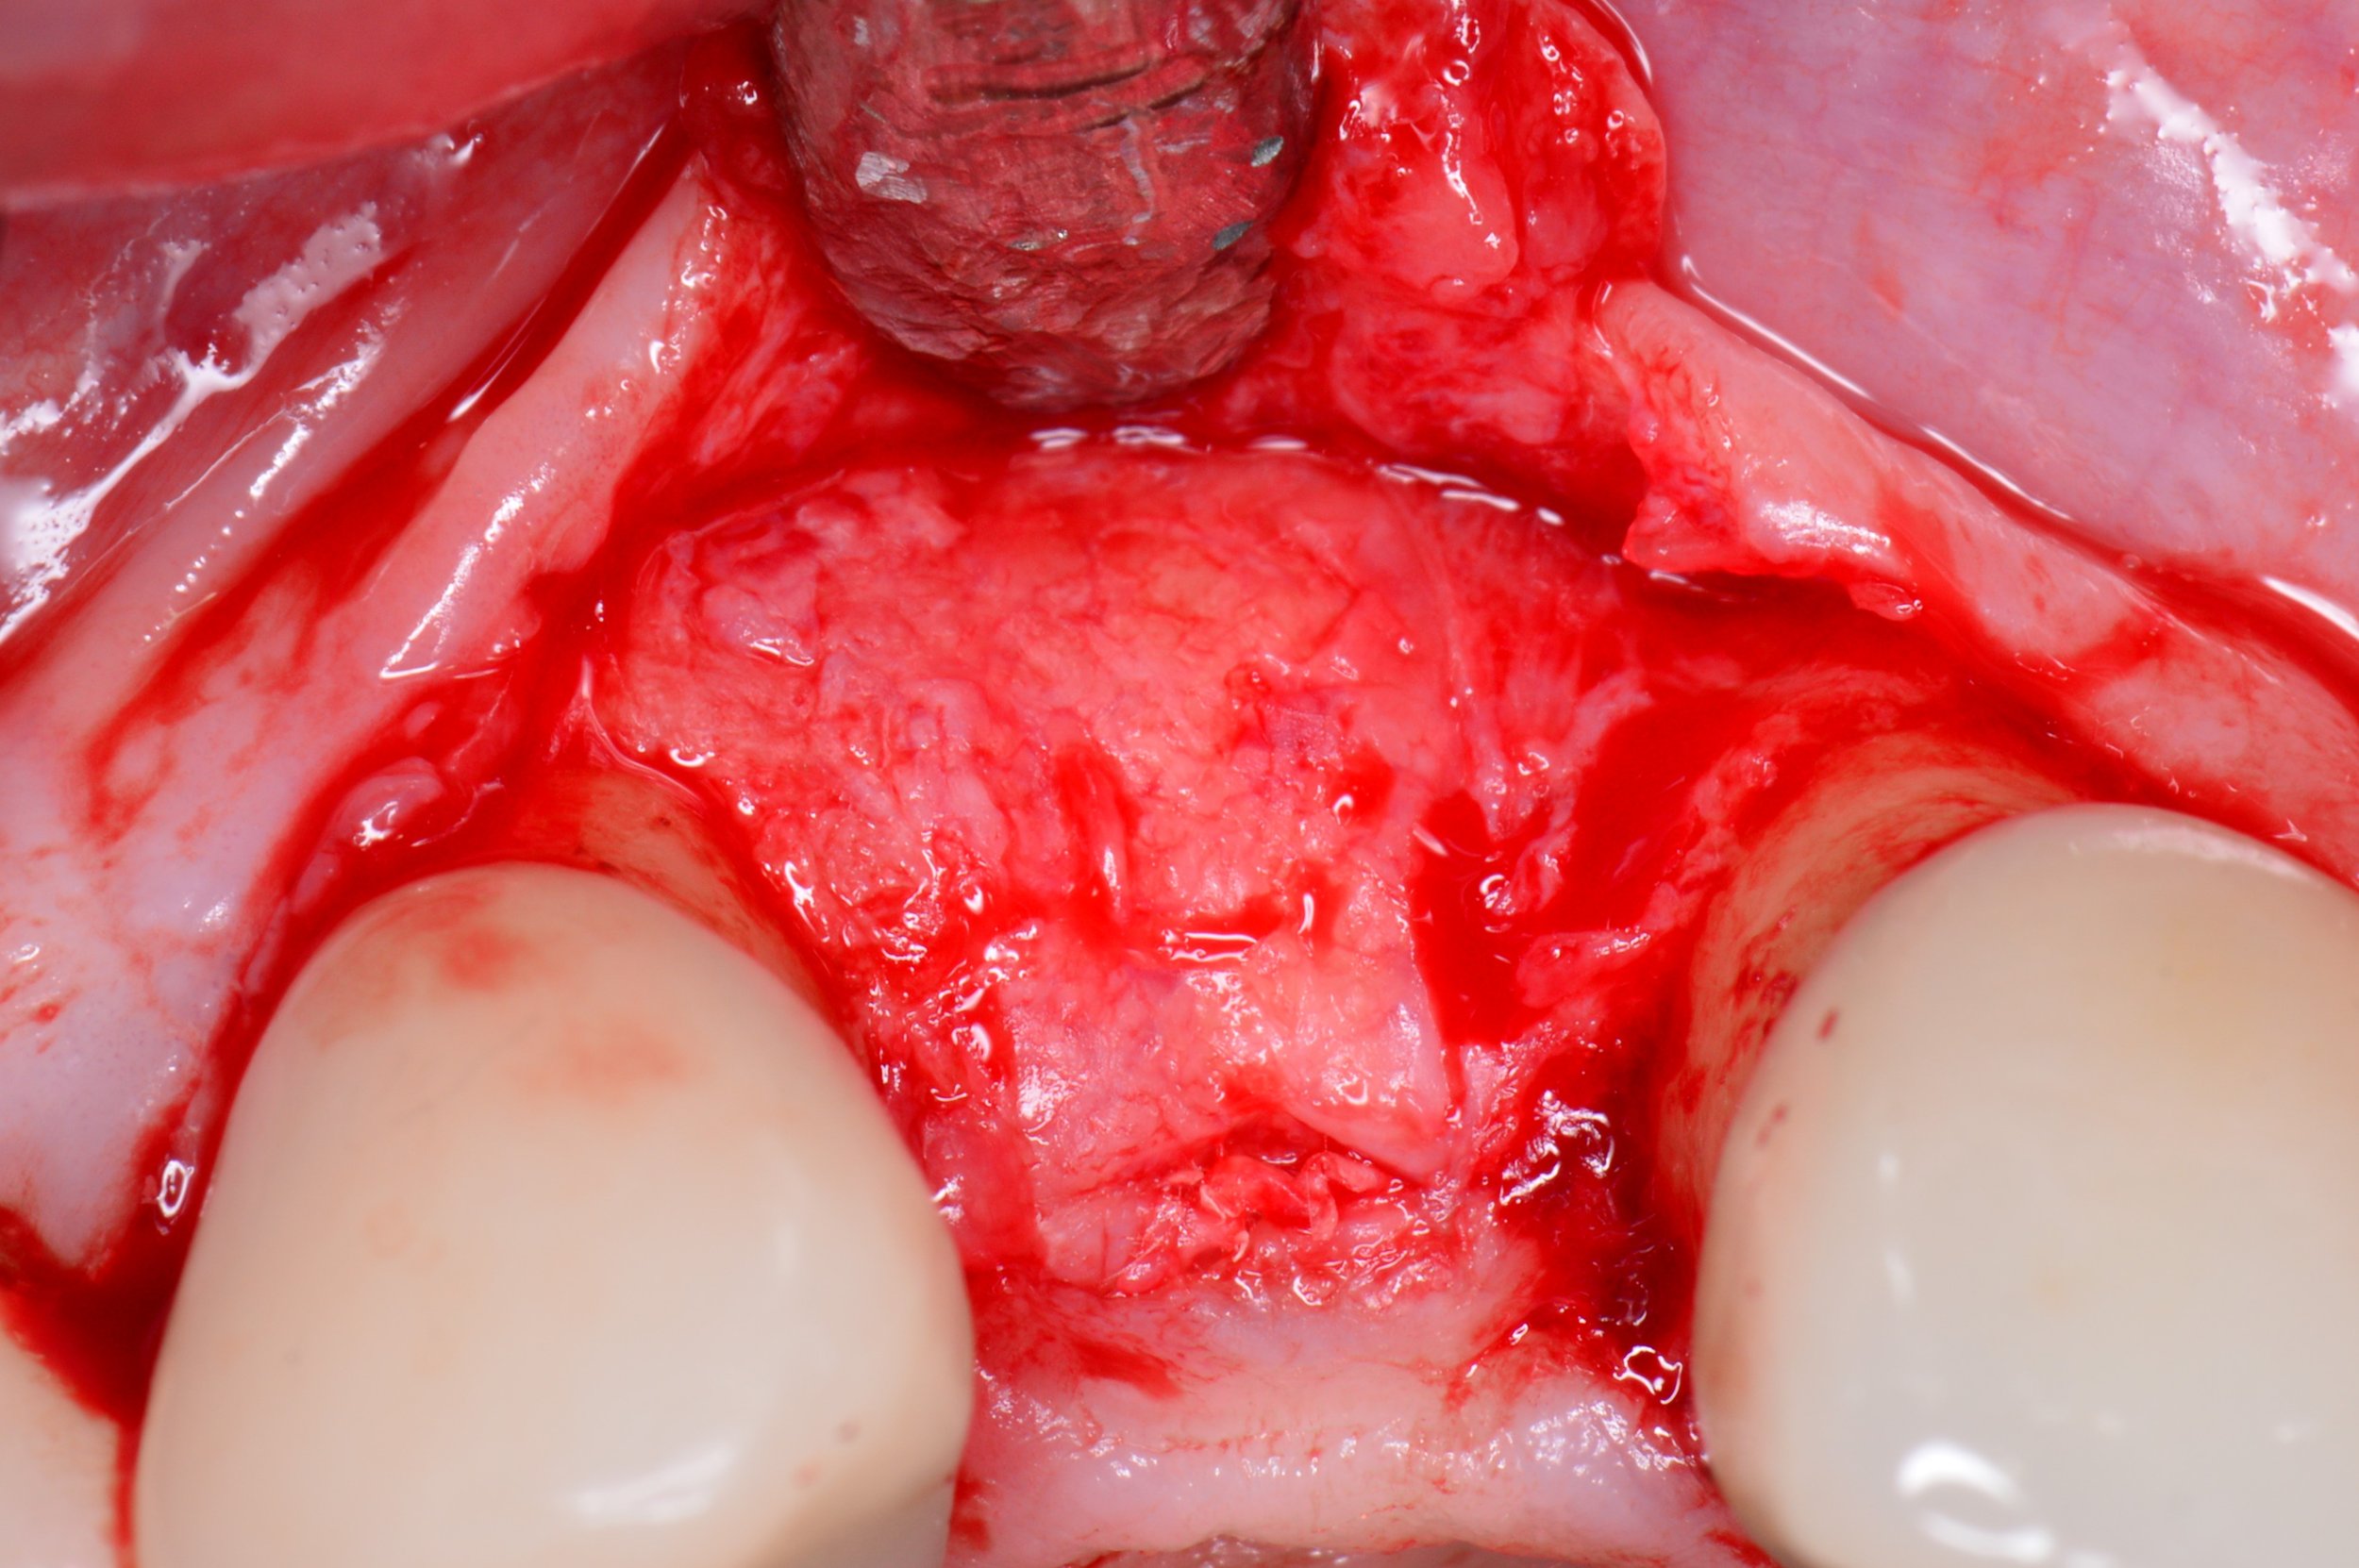

1. Placement: The grafting material is placed precisely where more bone is needed.

2. Protection: A small, dissolvable or removable membrane is placed over the graft to keep gum tissue out and let bone cells grow undisturbed.